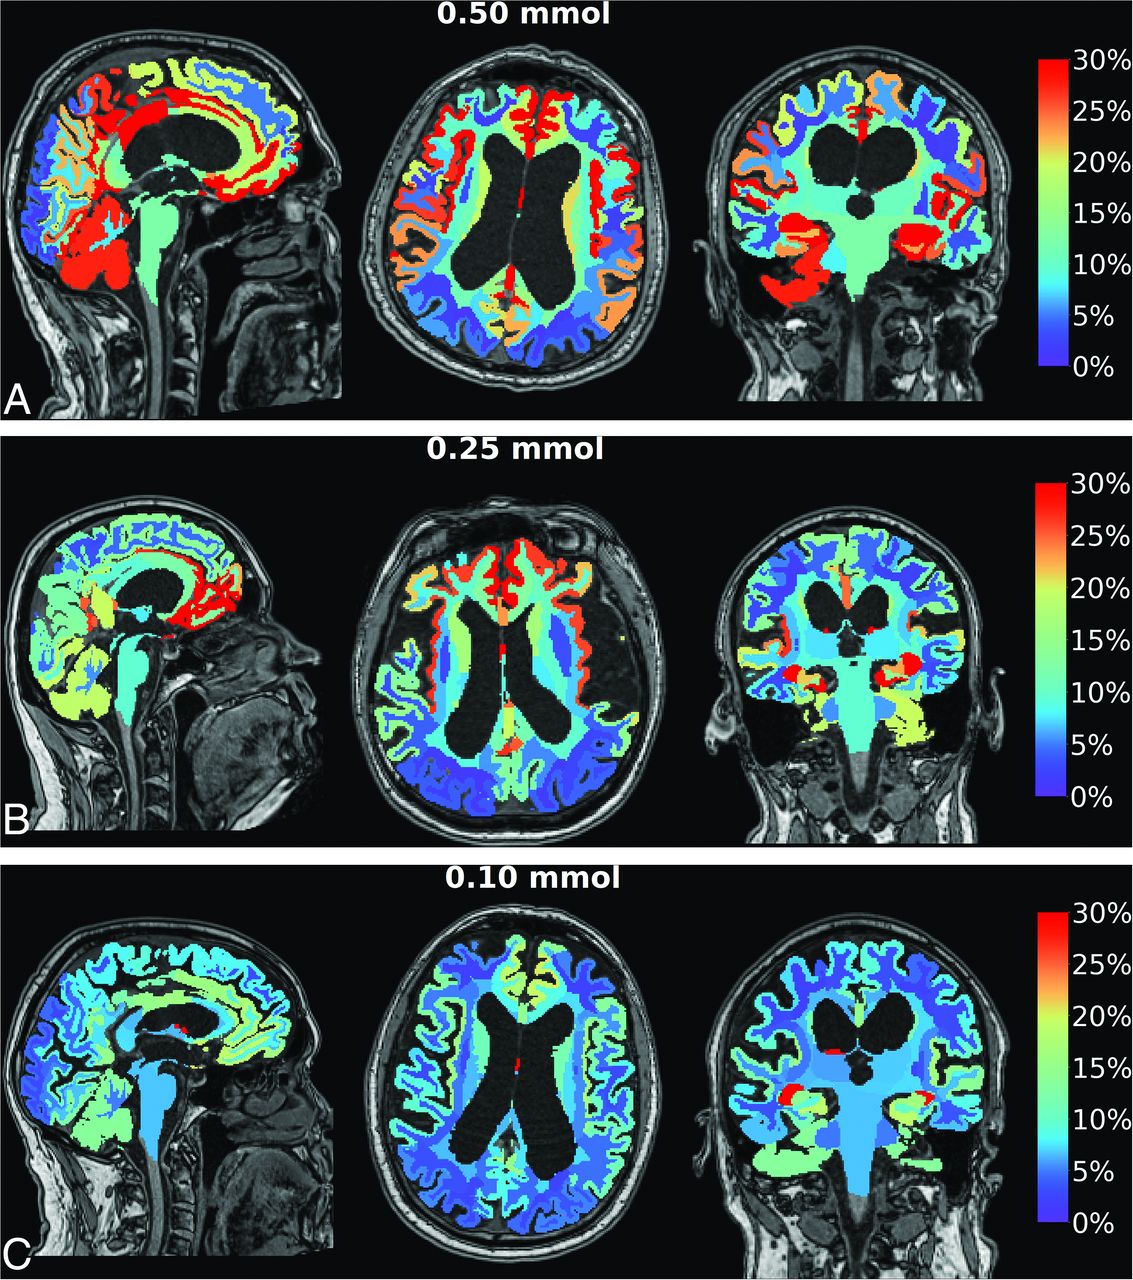

Contrast enrichment in the cranial CSF spaces was verified in all patients by observation of any T1 signal enhancement in the cranial CSF spaces on MR imaging. Figure 1 shows contrast enrichment in the brain after 24 hours in patients with iNPH, depending on the dose of intrathecal gadobutrol, visualized by 1.5T MR imaging. The contrast enhancement in the ventricles is shown in Fig 2.

Enrichment in the brain by gadobutrol, used as a CSF tracer, in patients with iNPH. Axial, sagittal, and coronal MR imaging visualizes dose-dependent brain-wide tracer enrichment 24 hours after intrathecal gadobutrol in the iNPH cohort examined with 1.5T MR imaging at a group level in which intrathecal gadobutrol was given in the doses of 0.50 mmol (n = 19) (A), 0.25 mmol (n = 68) (B), and (0.10 mmol (n = 26) (C). The percentage change in normalized T1 signal at 24 hours is shown on the color bar. In these images, tracer enrichment in the CSF is removed, demonstrating dose-dependent brain-wide tracer enrichment. The tracer enriches the brain centripetally from outside and inward. With 1.5T MR imaging, intrathecal gadobutrol in a dose of 0.10 mmol is not useful for diagnostic imaging, while the doses 0.25 and 0.50 mmol are adequate.

Accumulating evidence indicates the benefits of administering GBCA intrathecally. For years, clinicians have used intrathecal GBCA for visualization of CSF leakage in individuals with spontaneous intracranial hypotension.15,16 In our clinical practice, we have also used gMRI for the diagnostic assessment of ventricular reflux (Fig 2) and for estimation of impaired molecular clearance from intracranial CSF spaces and the brain (Fig 1). Hence, we have reported its utility in iNPH,10 idiopathic intracranial hypertension,17 and chronic sleep disturbance.18 Currently, we consider intrathecal contrast-enhanced MR imaging the criterion standard for imaging of glymphatic function, providing information not obtained by other imaging modalities. In a previous study, we showed that intrathecal gadobutrol in a dose of 0.25 mmol (but not 0.10 mmol) is sufficient for gMRI in iNPH using a 1.5T MR imaging scanner.11 When intrathecal gadobutrol is given for the assessment of CSF-to-blood clearance capacity, a dose of 0.10 mmol is sufficient.19